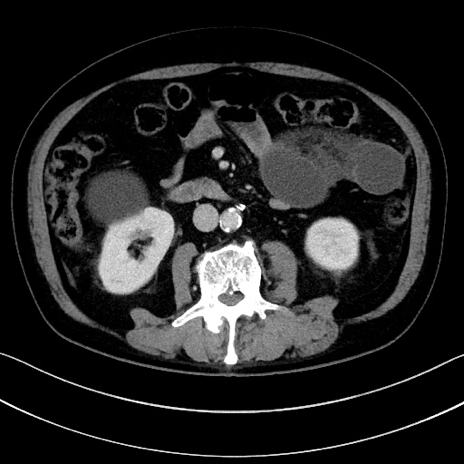

症例15(横断像)

【症例】70歳代男性

【主訴】腹痛

【現病歴】今朝から腹痛あり。全体的に痛い。特に左上の方。排ガスが今日はない。冷や汗が出る。

【既往歴】直腸癌術後

【身体所見】左側腹部〜上腹部に圧痛あり。腹膜刺激症状明らかなではない。軽度反跳痛。左下腹部に術後瘢痕あり。

【データ】WBC 7700、CRP 0.02